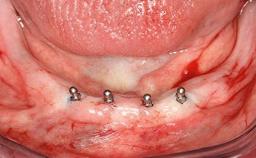

In 2007, a 97-year-old patient presented for treatment at the Geneva Dental School. His dentist had retired. Like many elderly patients, he was left without regular dental care. He lived on a geriatric ward, as he was partly dependent on help with most of the activities of daily living (ADL), such as getting dressed, washing, taking a shower, or climbing stairs. However, he was able to go to the bathroom and get up from bed on his own (ADL score 80, min. 18, max. 126; a low score signifies a high degree of dependency) (Lawton and Brody 1969). He was not bound to a wheelchair, but used a walker. Moreover, he was socially highly active—his family visited on a regular basis and he often went to the restaurant with his friend, who was some 20 years younger. His cognitive function did not seem to be impaired in a normal conversation, although his MMSE score was only 21/30 at that time (Folstein and coworkers 1975). The patient was a retired pharmacist, and his latest passion was astronomy.